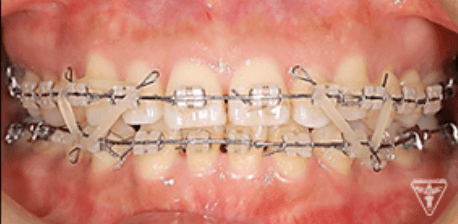

治療後